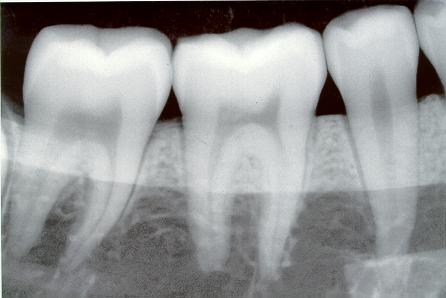

Radiografías dentales se relacionan a meningiomas

¿Qué debe hacer la próxima vez cuando el dentista le diga que debe tomarse una radiografía dental completa? Un nuevo estudio demuestra que debe limitar la cantidad de exposición a la radiación en el transcurso de...